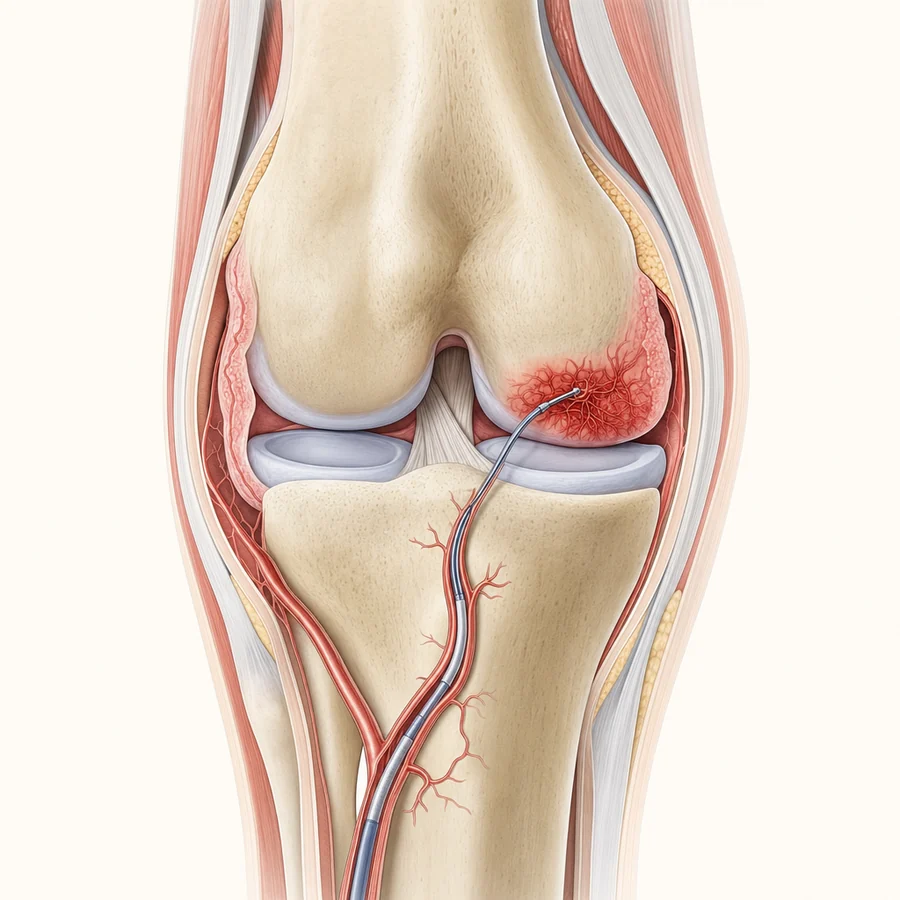

1How GAE Works · Step 1 of 4

The problem: abnormal blood vessels

In a knee with osteoarthritis, the inflamed joint lining (the synovium) grows extra, abnormal blood vessels. That excess blood flow feeds ongoing inflammation, which is a major driver of knee pain.